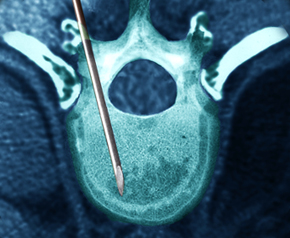

안정과 휴식을 취하면서 약물치료, 주사치료, 운동치료, 도수치료, 체외충격파 등을 복합적으로 시행합니다. 비수술치료시 신경차단술, 신경성형술, 협착부위 풍선확장술 등을

통해 질환을 호전시 킵니다.

비수술 치료에도 증상이 호전되지 않거나 보행 장애가 심각한 등 일상생활에 지장이 있다면 수술 치료를 시행하하며 양방향척추내시경 및 미세현미경레이져수술,

척추유합술 등을 통해 치료합니 다.